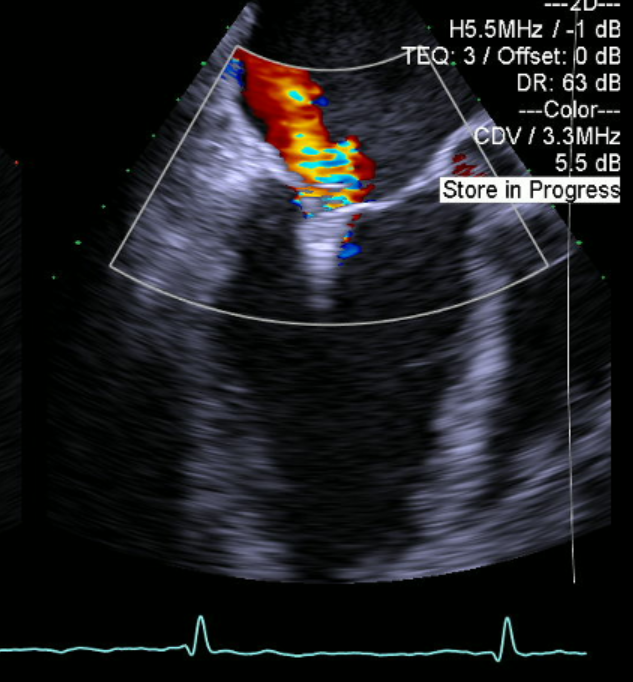

患者麻醉方式为全麻,建立静脉通路后,穿刺右侧股静脉,食道超声和透视辅助下成功穿刺房间隔,将导丝送至左房。使用血管鞘扩张股静脉后,经导丝导入24F导引鞘管跨过房间隔至左心房,通过24F导引鞘管送入二尖瓣MitraClip瓣膜夹系统(CDS),在食道超声引导下顺利到达二尖瓣目标位置并捕获连枷瓣叶。经食道超声反复确认后,在二尖瓣A2/P2偏3区处植入一枚MitraClip XTR二尖瓣瓣膜夹,食道超声检查见瓣膜夹位置良好,瓣叶抓捕牢固。术后即刻超声提示二尖瓣反流下降至微量,二尖瓣平均跨瓣压3mmHg,多切面证实夹合组织充分,左上肺静脉多普勒波形由反向恢复正常。手术效果理想,逐步释放瓣膜夹系统撤出体外。

彩色血流提示微量的瓣膜反流,测量平均跨瓣压差3mmHg